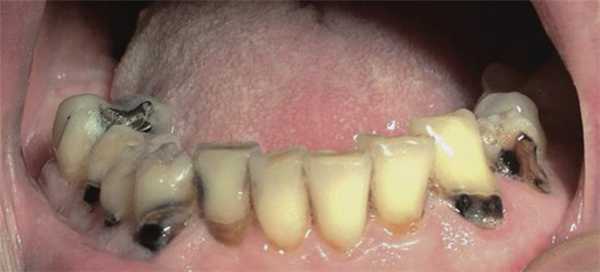

Также при ксеростомии возникают новые и рецидивируют существующие участки кариозного поражения, при этом пожилые пациенты являются наиболее уязвимыми к подобным осложнениям, поскольку большее количество их собственных зубов уже подвергалось стоматологическому лечению, а в пришеечной области таковых часто наблюдаются участки рецессии десен. Особенно часто рецессии возникают со щечной поверхности ранее восстановленных фронтальных зубов (фото 1).

Фото 1. Вид полости рта пациента с острыми кариозными поражениями вестибулярных и пришеечных поверхностей зубов, вызванные долгосрочным приемом антихолинергических препаратов.